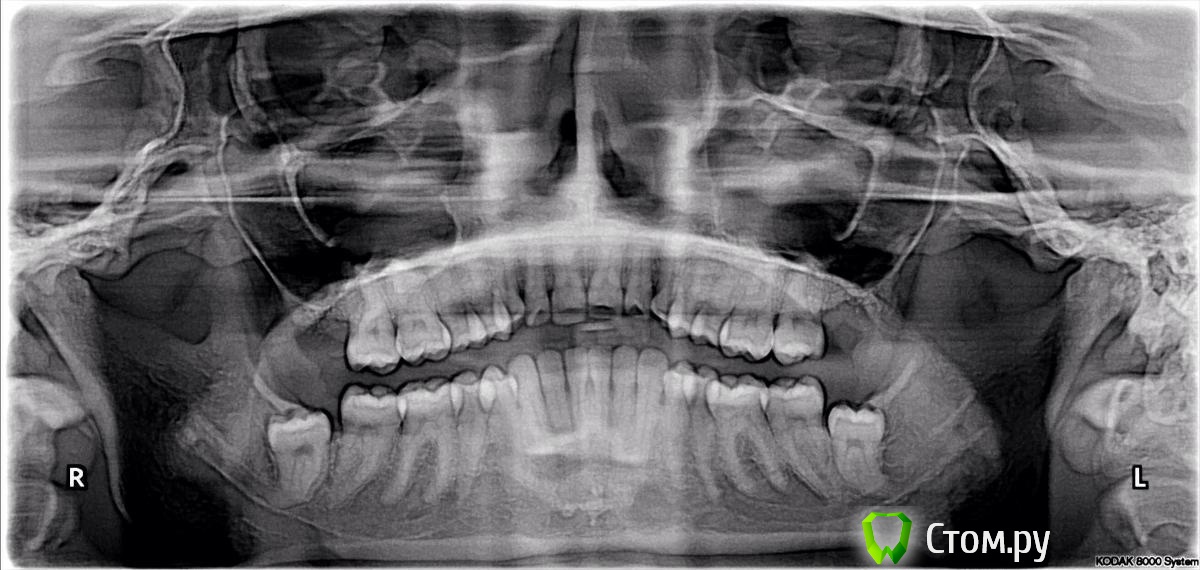

Ketherin Опубликовано 19 февраля, 2014 Поделиться Опубликовано 19 февраля, 2014 Здраствуйте!Нижние зубы мудрости не беспокоят, но если удалять то по рентгену видно, что может быть задет нижний нерв. Очень большая вероятность онемения?Удаление неизбежно? Ссылка на комментарий

diesel87 Опубликовано 19 февраля, 2014 Поделиться Опубликовано 19 февраля, 2014 Здравствуйте, по снимку 8ки расположены пока на безопасном расстоянии от 7ок,если все же запланируется удаление то у грамотного хирурга весь прием не займет больше 40 минут, по поводу онемения не факт,все зависит от атравматичности удаления. Ссылка на комментарий

diesel87 Опубликовано 19 февраля, 2014 Поделиться Опубликовано 19 февраля, 2014 Риск 50 на 50? Стоит ли сделать КТ? Рентген 3D? Можно ли избежать удаления? Какой из зубов более опасно удалять?Больший риск травмы нижнечелюстного нерва при удалении правой 8ки, у левой корни расположены не в канале, но за ним, а почему вам их назначили на удаления, какие показания? Ссылка на комментарий

Ketherin Опубликовано 19 февраля, 2014 Автор Поделиться Опубликовано 19 февраля, 2014 Сказали, что лучше удалить до 35 лет, тогда меньший риск травмы, если в будущем возникнет карман между 7 и 8 зубами, как раз справа, тогда кариес и тп и тд. Мне сейчас 27 и неизвестно вырастет ли корень еще глубже в канал. А сейчас пока они не беспокоят, хотя бугорки на деснах есть. Жаль, что у меня так все плохо с нервом и каналом.. Ссылка на комментарий

Bier Опубликовано 20 февраля, 2014 Поделиться Опубликовано 20 февраля, 2014 корень у Вас уже вырос и больше никуда расти не будет.Надо посмотреть на КТ, если корень не в канале, то риск не очень велик. 1 Ссылка на комментарий